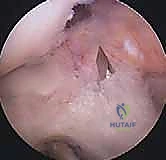

الخطوة الأولى: الفحص بالمنظار الجراحي 4K

يستخدم الدكتور